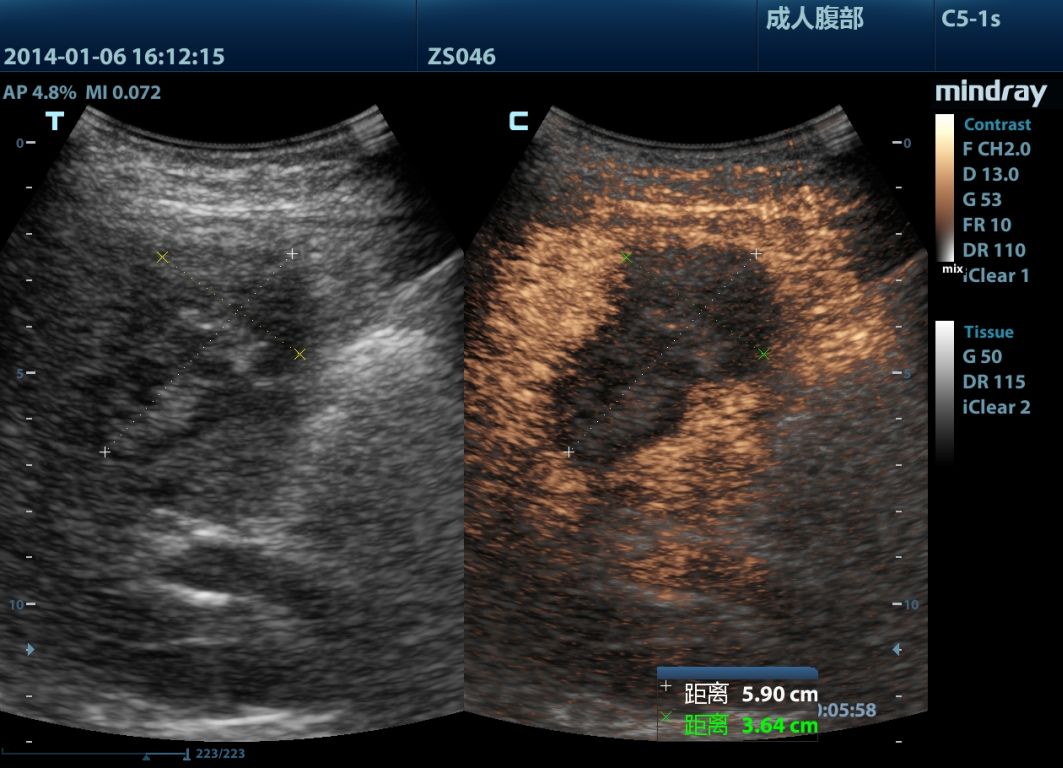

Mindray M9 je dopplerovský ultra ľahký prenosný UZV prístroj najvyššej High End triedy s použitím single crystal 3T sond (vynikajúce zobrazenie blízkeho i vzdialeného poľa), HDR FLOW, ECHO BOOST, Natural Touch Elastography, kontrastného zobrazenia, TDI. Špeciál hlavne pre kardiológiu.

Klinické obrázky: